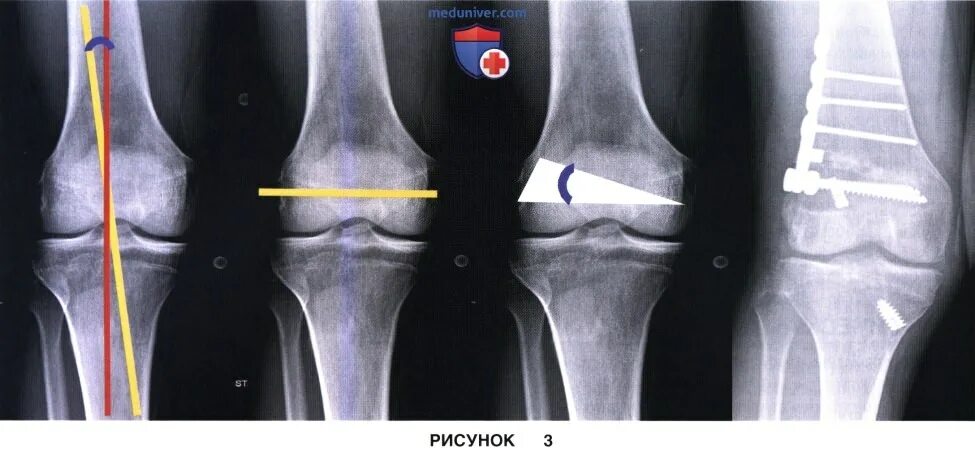

Перелом коленного сустава мкб